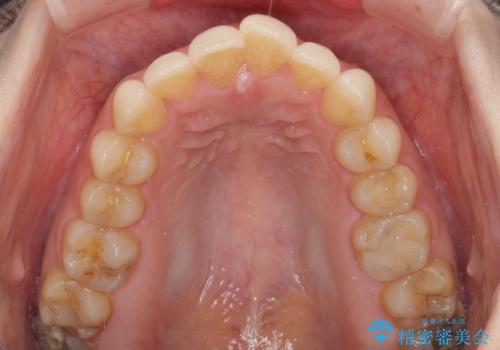

- 上下の前歯のデコボコを気にして来院された患者様です。

上下顎歯列全体の後方移動とIPR(歯と歯の間を削る)によってデコボコが解消するように設計しました。